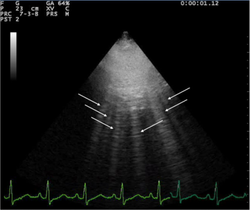

- Appear as horizontal lines

- Indicate dry interlobular septa.

- Predominance of A lines has 90% sensitivity, 67% specificity for pulmonary artery wedge pressure <= 13mm Hg

- A line predominance suggests that intravenous fluids may be safely given without concern for pulmonary edema

- B lines ("comets"):

- White lines from the pleura to the bottom of the screen

- Highly sensitive for pulmonary edema, but can be present at low wedge pressures